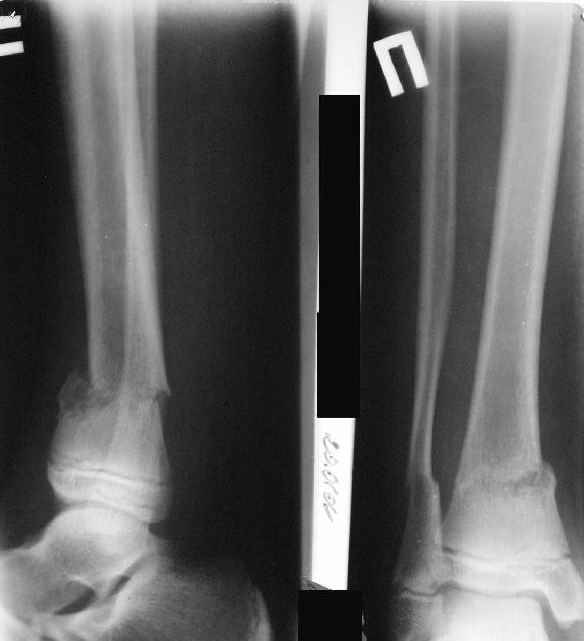

В январе 2005: варусная деформация н\3 голени, болевой с-м, комбинированная контрактура г\стопного сустава, нейропатия м\берцового нерва сохраняется слабость разгибания 1 пальца.

A> В январе 2005: варусная деформация н\3 голени,

А на вытяжении и в гипсповязке в течение 4 мес варуса видно не было?

Фиксация

|

в гипсе